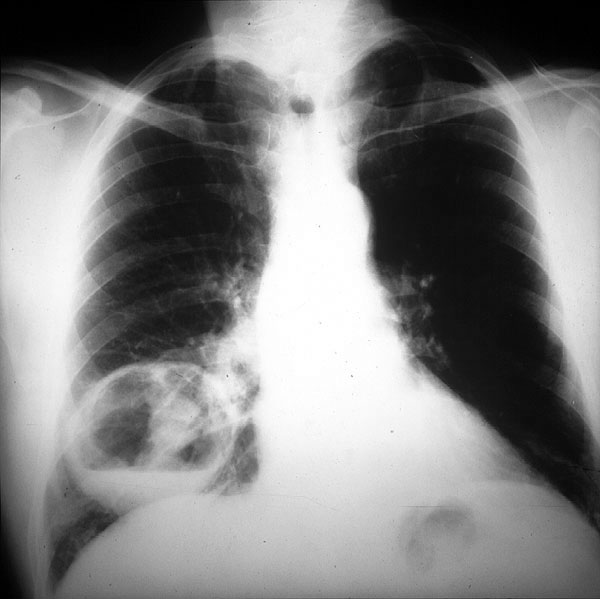

Placa 32